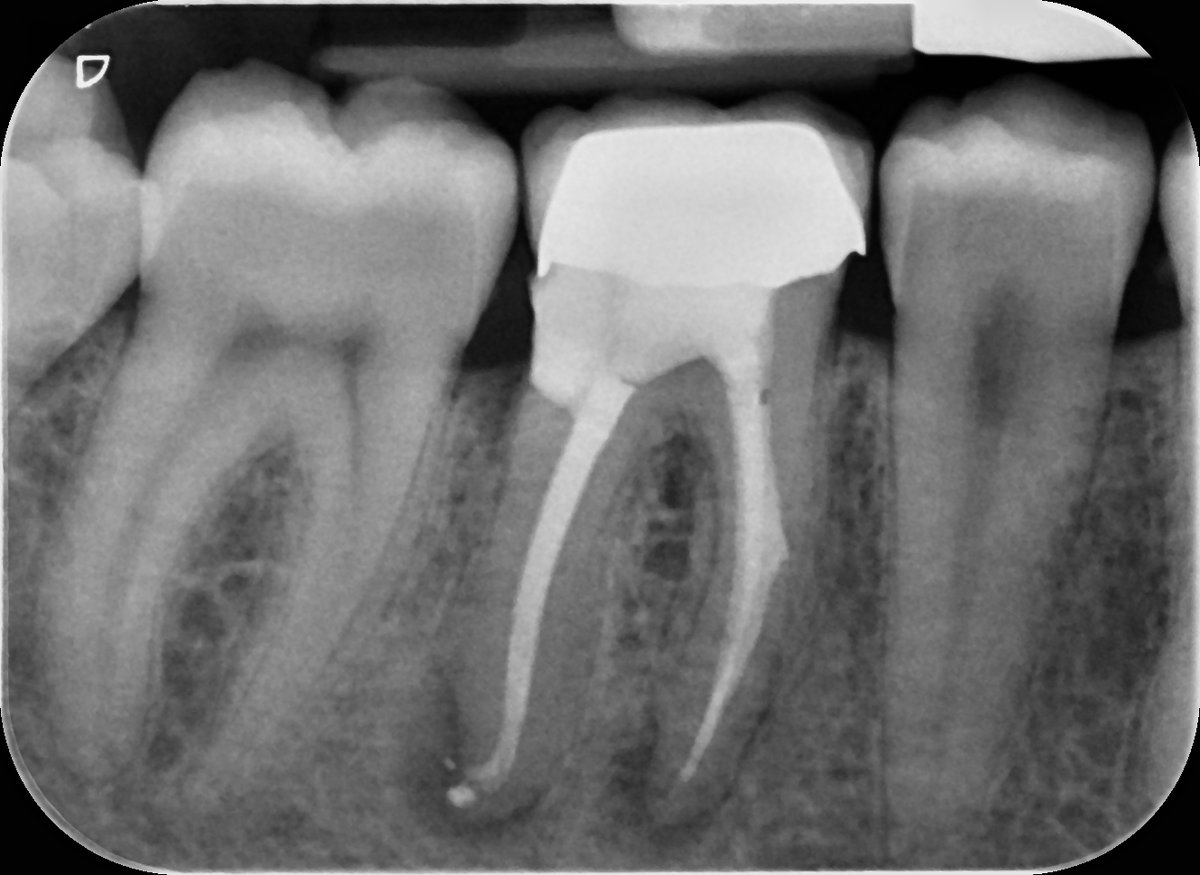

2-visit reRCT UR6 - insane apical delta anatomy P and MB canals - all thanks to the power of hypochlorite!🤣 Edge Endo preps VC obturation #savingteeth #endodontics

2-visit reRCT UR6 - insane apical delta anatomy P and MB canals - all thanks to the power of hypochlorite!🤣

Edge Endo preps VC obturation #savingteeth #endodontics